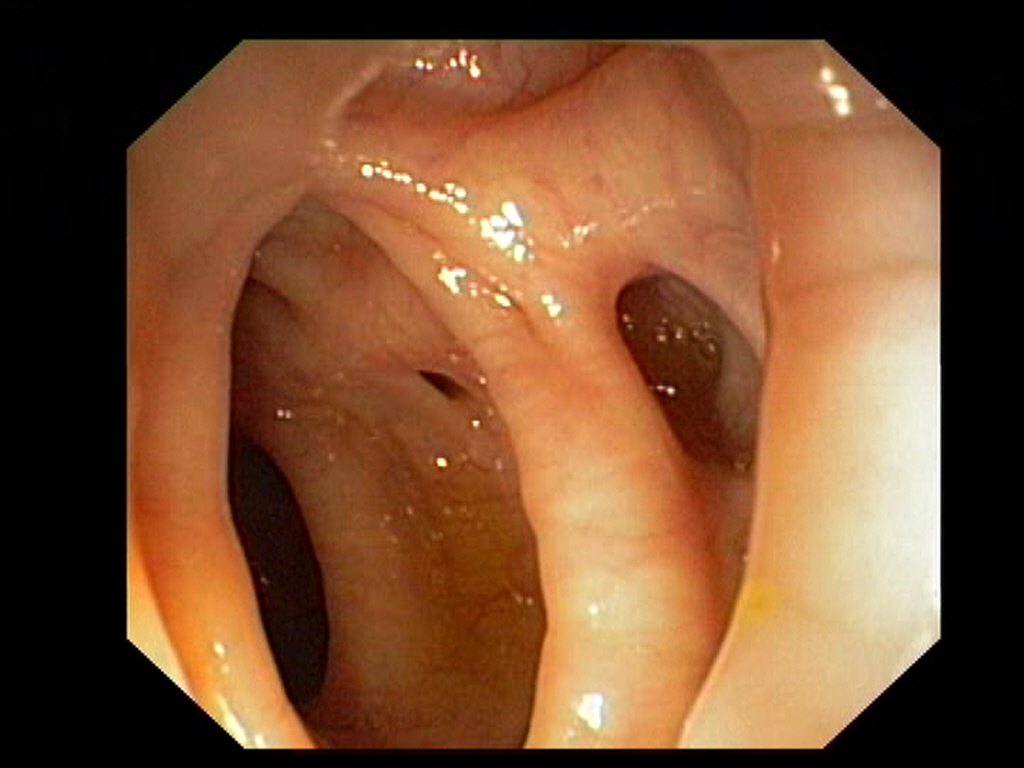

Diverticulosis in the Sigmoid Colon

Diverticulosis in the Sigmoid ColonJust click on a picture!